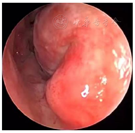

口腔检查:口腔颌面部左右不对称,左侧鼻旁区明显隆起,按压乒乓球样感,双侧颞下颌关节无弹响,无压痛。口内见12-23前庭沟处膨隆,大小约4.2 cm×2.0 cm,边界清,质软,有轻微压痛,22-24腭侧球形膨隆,大小约1.5 cm×1.5 cm,边界清,质软,可触及波动感,无压痛。22唇侧有一瘘管,挤压有脓液溢出。鼻内镜检查:鼻腔黏膜略充血,左侧鼻底及下鼻道见明显隆起(图4),将左侧下鼻甲推向外上方,鼻中隔向右侧偏曲,左侧鼻道较宽敞,中鼻道略隆起,未见分泌物。CBCT示:12-24根尖区可见3.7 cm×1.6 cm大小的低密度影像,边界清楚,密度均匀,内见不完全的骨间隔影,肿物累及左侧鼻底及鼻腔外侧壁,左侧上颌窦内见液平面。

入院后完善术前常规检查,于次日在局麻下行切开引流术,阿替卡因肾上腺素行21-22前庭沟黏膜下局部浸润麻醉,麻醉显效后,自21-22前庭沟处切开黏膜及黏膜下层至囊腔约3 mm水平切口,见大量黄色分泌物溢出,取部分脓液做细菌培养,大量生理盐水冲洗至冲洗,留置橡皮引流条,术后常规予以抗生素控制感染。4 d后检查前庭沟切口处已愈合。经耳鼻咽喉科与口腔颌面外科会诊,决定行鼻内镜下左侧鼻底、下鼻道共同开窗肿物切除术。术中先用彭氏电刀电凝左侧鼻底及下鼻道隆起处黏膜(图5),剥离子自隆起处外侧刺破黏膜进入囊腔,见大量囊液流出,囊液呈浅褐色,略浑浊,吸净囊液后,向后扩大开窗口,保留后部黏膜瓣。剥离部分囊壁送病理检查,清除病变组织后,发现位于囊腔前下壁的不完全的骨间隔隆起(图6)。剥离子在囊肿的左侧上部探查见上颌窦内下骨质缺损,由此刺破软组织进入上颌窦,见有黏液涕流出,扩大上颌窦开窗口,动力系统清除病变组织,使囊肿腔与上颌窦形成一个腔(图7),修剪后部蒂瓣,使之正好贴敷于囊腔后壁(图8),反复生理盐水冲洗术腔,检查无残留,膨胀海绵填塞。手术过程见视频。手术顺利,术后继续行抗生素控制感染,48 h抽出鼻腔膨胀海绵,检查见鼻底及上颌窦开窗口开放良好,腔内有少许血性分泌物,黏膜略水肿。术后病理镜下见被覆鳞状上皮,间质内见急慢性细胞浸润(图9)。术后4 d患者康复出院。